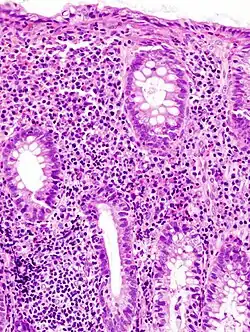

Pathologie/Morphologie

- Bei einem milden Verlauf kommt es zur ödematösen Schwellung der Darmschleimhaut.

- Bei mittleren Verlaufsformen kommt es zu leichten Blutungen und Geschwürsbildungen.

- Bei schweren Verläufen kommt es zu großflächigen Geschwürsbildungen, die zum Verlust des Reliefs und zur Schleimhautabflachung führen. Durch überschießende Regeneration kommt es zur Bildung von Pseudopolypen. Feingeweblich (histologisch) fallen Lymphozyten und Histiozyten auf, während die Zahl der Becherzellen stark vermindert ist. Als typisch, wenn auch nicht beweisend, gelten Kryptenabszesse.

- Im akuten schwersten Verlauf kann es zur toxischen Dickdarmerweiterung kommen. Dabei findet sich eine Überblähung des Bauchraumes und eine Bauchfellentzündung, außerdem besteht die Gefahr einer Perforation, weshalb jegliche invasive Diagnostik kontraindiziert ist.